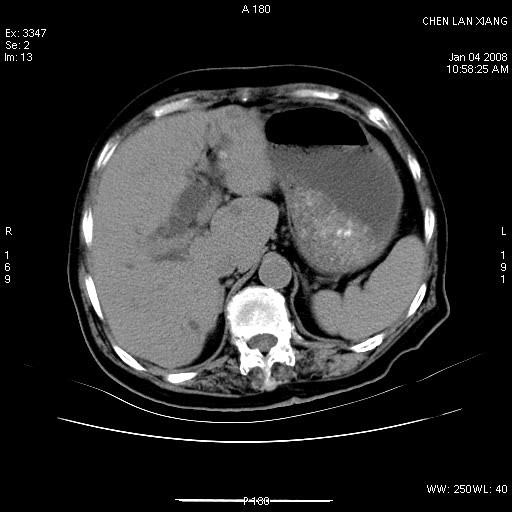

女,76岁,腹痛3-4天,b超示:肝内实性肿物,胆囊强回声,胆总管扩张.

考虑:1、胆总管下端结石伴梗阻性肝内外胆管扩张(肝左叶外侧段肝内胆管多发结石、胆管炎);

2、肿囊癌累及肝,不除外 黄色肉芽肿性胆囊炎。

1 胆总管末端结石伴肝内胆管结石,肝内外胆管扩张。2 胆囊扩大,胆囊壁不规则增厚,内见软组织密度影。考虑:慢性胆囊炎,不除外胆囊癌!

胆囊内结增强影,肝内胆管、胆总管扩张明显。肝内胆管、胆总管下段多发结石,胆囊癌,建议mrcp检查

肝内外胆管多发结石;胆囊癌;

ct所见:1、 肝内胆管结石,肝内外胆管扩张。低位胆道梗阻,胆总管下端结石;2 胆囊扩大,胆囊壁不规则增厚

考虑:胆总管下端结石并肝内外胆管扩张,肝内胆管结石;

标题: 肝右叶病灶

胆囊癌侵犯肝右叶?

1)胆囊癌伴肝脏转移。2)胆总管下端结石、肝内胆管结石伴肝内外胆管扩张。